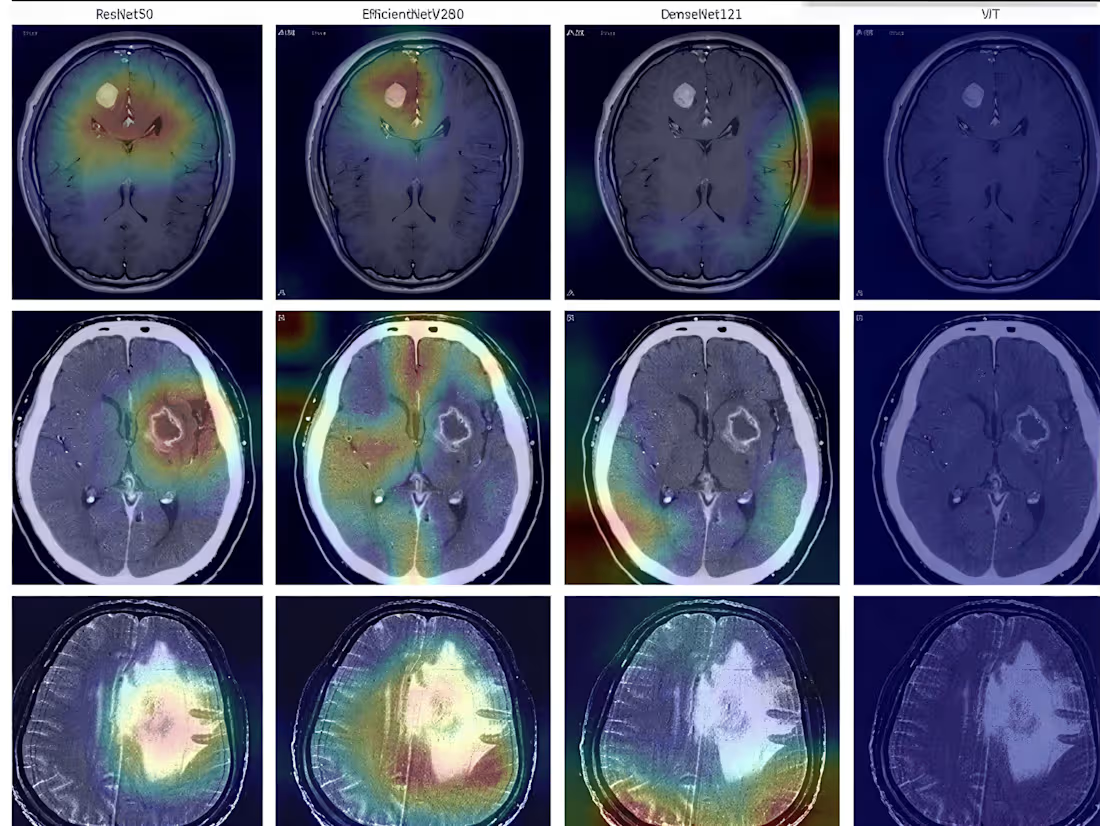

"Beyond the Scan: Enhancing Brain Tumor Detection through AI Visualization"

"Medical scans can be incredibly complex, so I conducted a comparative failure analysis to see how different AI 'brains'—like ResNet50 and Vision Transformers—interpret them. By using heatmap visualizations (as seen in the image), I’ve made it easier to see exactly where a model succeeds or struggles, aiming to make AI-assisted diagnostics more reliable and transparent."🧠